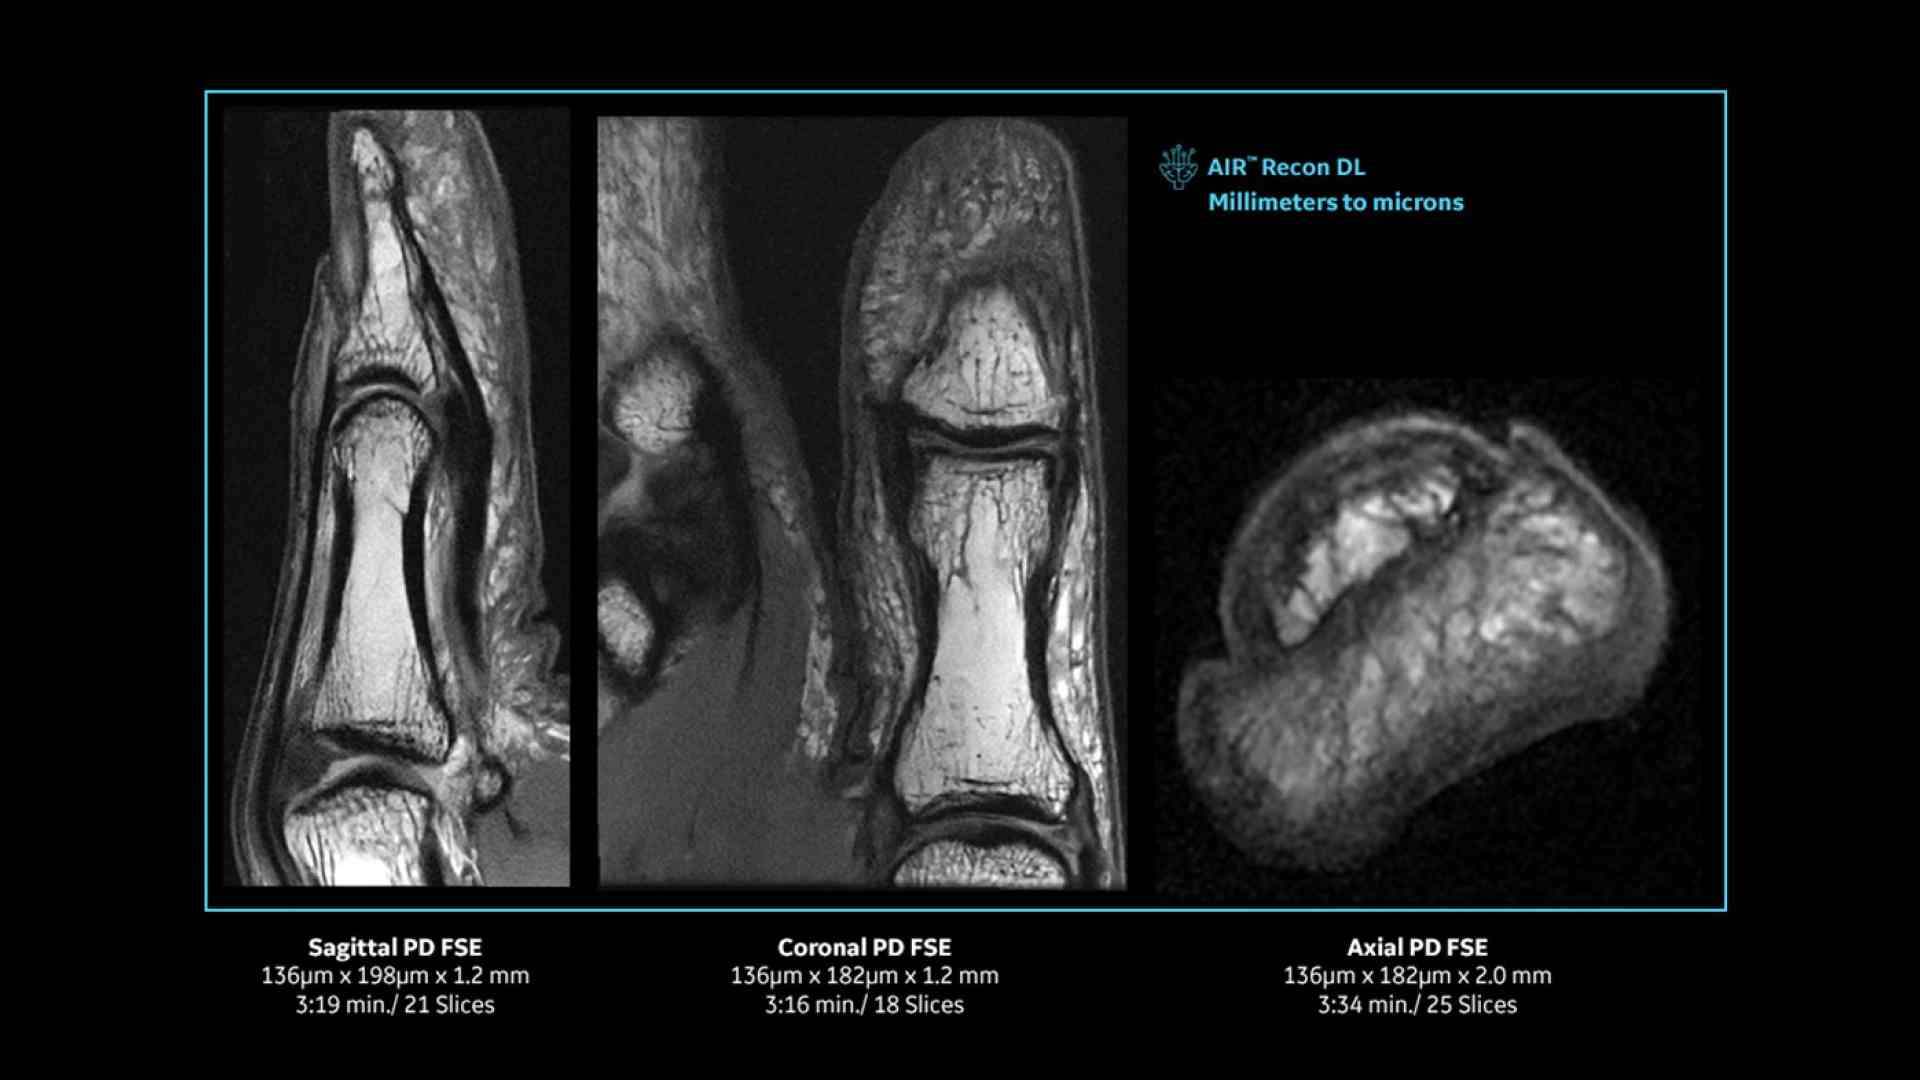

Revolutionary, deep-learning-based reconstruction techniques such as AIR™ Recon DL provide sharper, clearer, and accurate images

Pin-sharp image quality and exceptional speed with AIR™ Recon DL and Sonic™ DL​

SIGNA™ Premier offers the versatility you need to fulfill all your clinical needs. Explore the advanced imaging and clinical capabilities achievable with the SIGNA™ Premier system.

Experience pin-sharp precision and remarkable speed with a 3T SIGNA™ Premier MRI scanner, coupled with AIR™ Recon DL and Sonic™ DL.